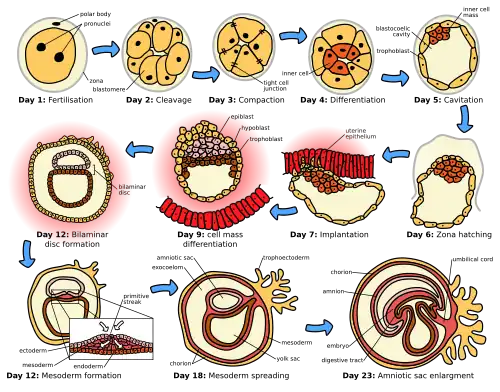

Prenatal development (from Latin natalis 'relating to birth') involves the development of the embryo and of the fetus during a viviparous animal's gestation. Prenatal development starts with fertilization, in the germinal stage of embryonic development, and continues in fetal development until birth. The term "prenate" is used to describe an unborn offspring at any stage of gestation.[1]

In human pregnancy, prenatal development is also called antenatal development. The development of the human embryo follows fertilization, and continues as fetal development. By the end of the tenth week of gestational age, the embryo has acquired its basic form and is referred to as a fetus. The next period is that of fetal development where many organs become fully developed. This fetal period is described both topically (by organ) and chronologically (by time) with major occurrences being listed by gestational age.

Following fertilization, the embryonic stage of development continues until the end of the 10th week (gestational age) (8th week fertilization age). The first two weeks from fertilization is also referred to as the germinal stage or preembryonic stage.[7]

The zygote spends the next few days traveling down the fallopian tube dividing several times to form a ball of cells called a morula. Further cellular division is accompanied by the formation of a small cavity between the cells. This stage is called a blastocyst. Up to this point there is no growth in the overall size of the embryo, as it is confined within a glycoprotein shell, known as the zona pellucida. Instead, each division produces successively smaller cells.

The blastocyst reaches the uterus at roughly the fifth day after fertilization. The blastocyst hatches from the zona pellucida allowing the blastocyst's outer cell layer of trophoblasts to come into contact with, and adhere to, the endometrial cells of the uterus. The trophoblasts will eventually give rise to extra-embryonic structures, such as the placenta and the membranes. The embryo becomes embedded in the endometrium in a process called implantation. In most successful pregnancies, the embryo implants 8 to 10 days after ovulation.[8] The embryo, the extra-embryonic membranes, and the placenta are collectively referred to as a conceptus, or the "products of conception".